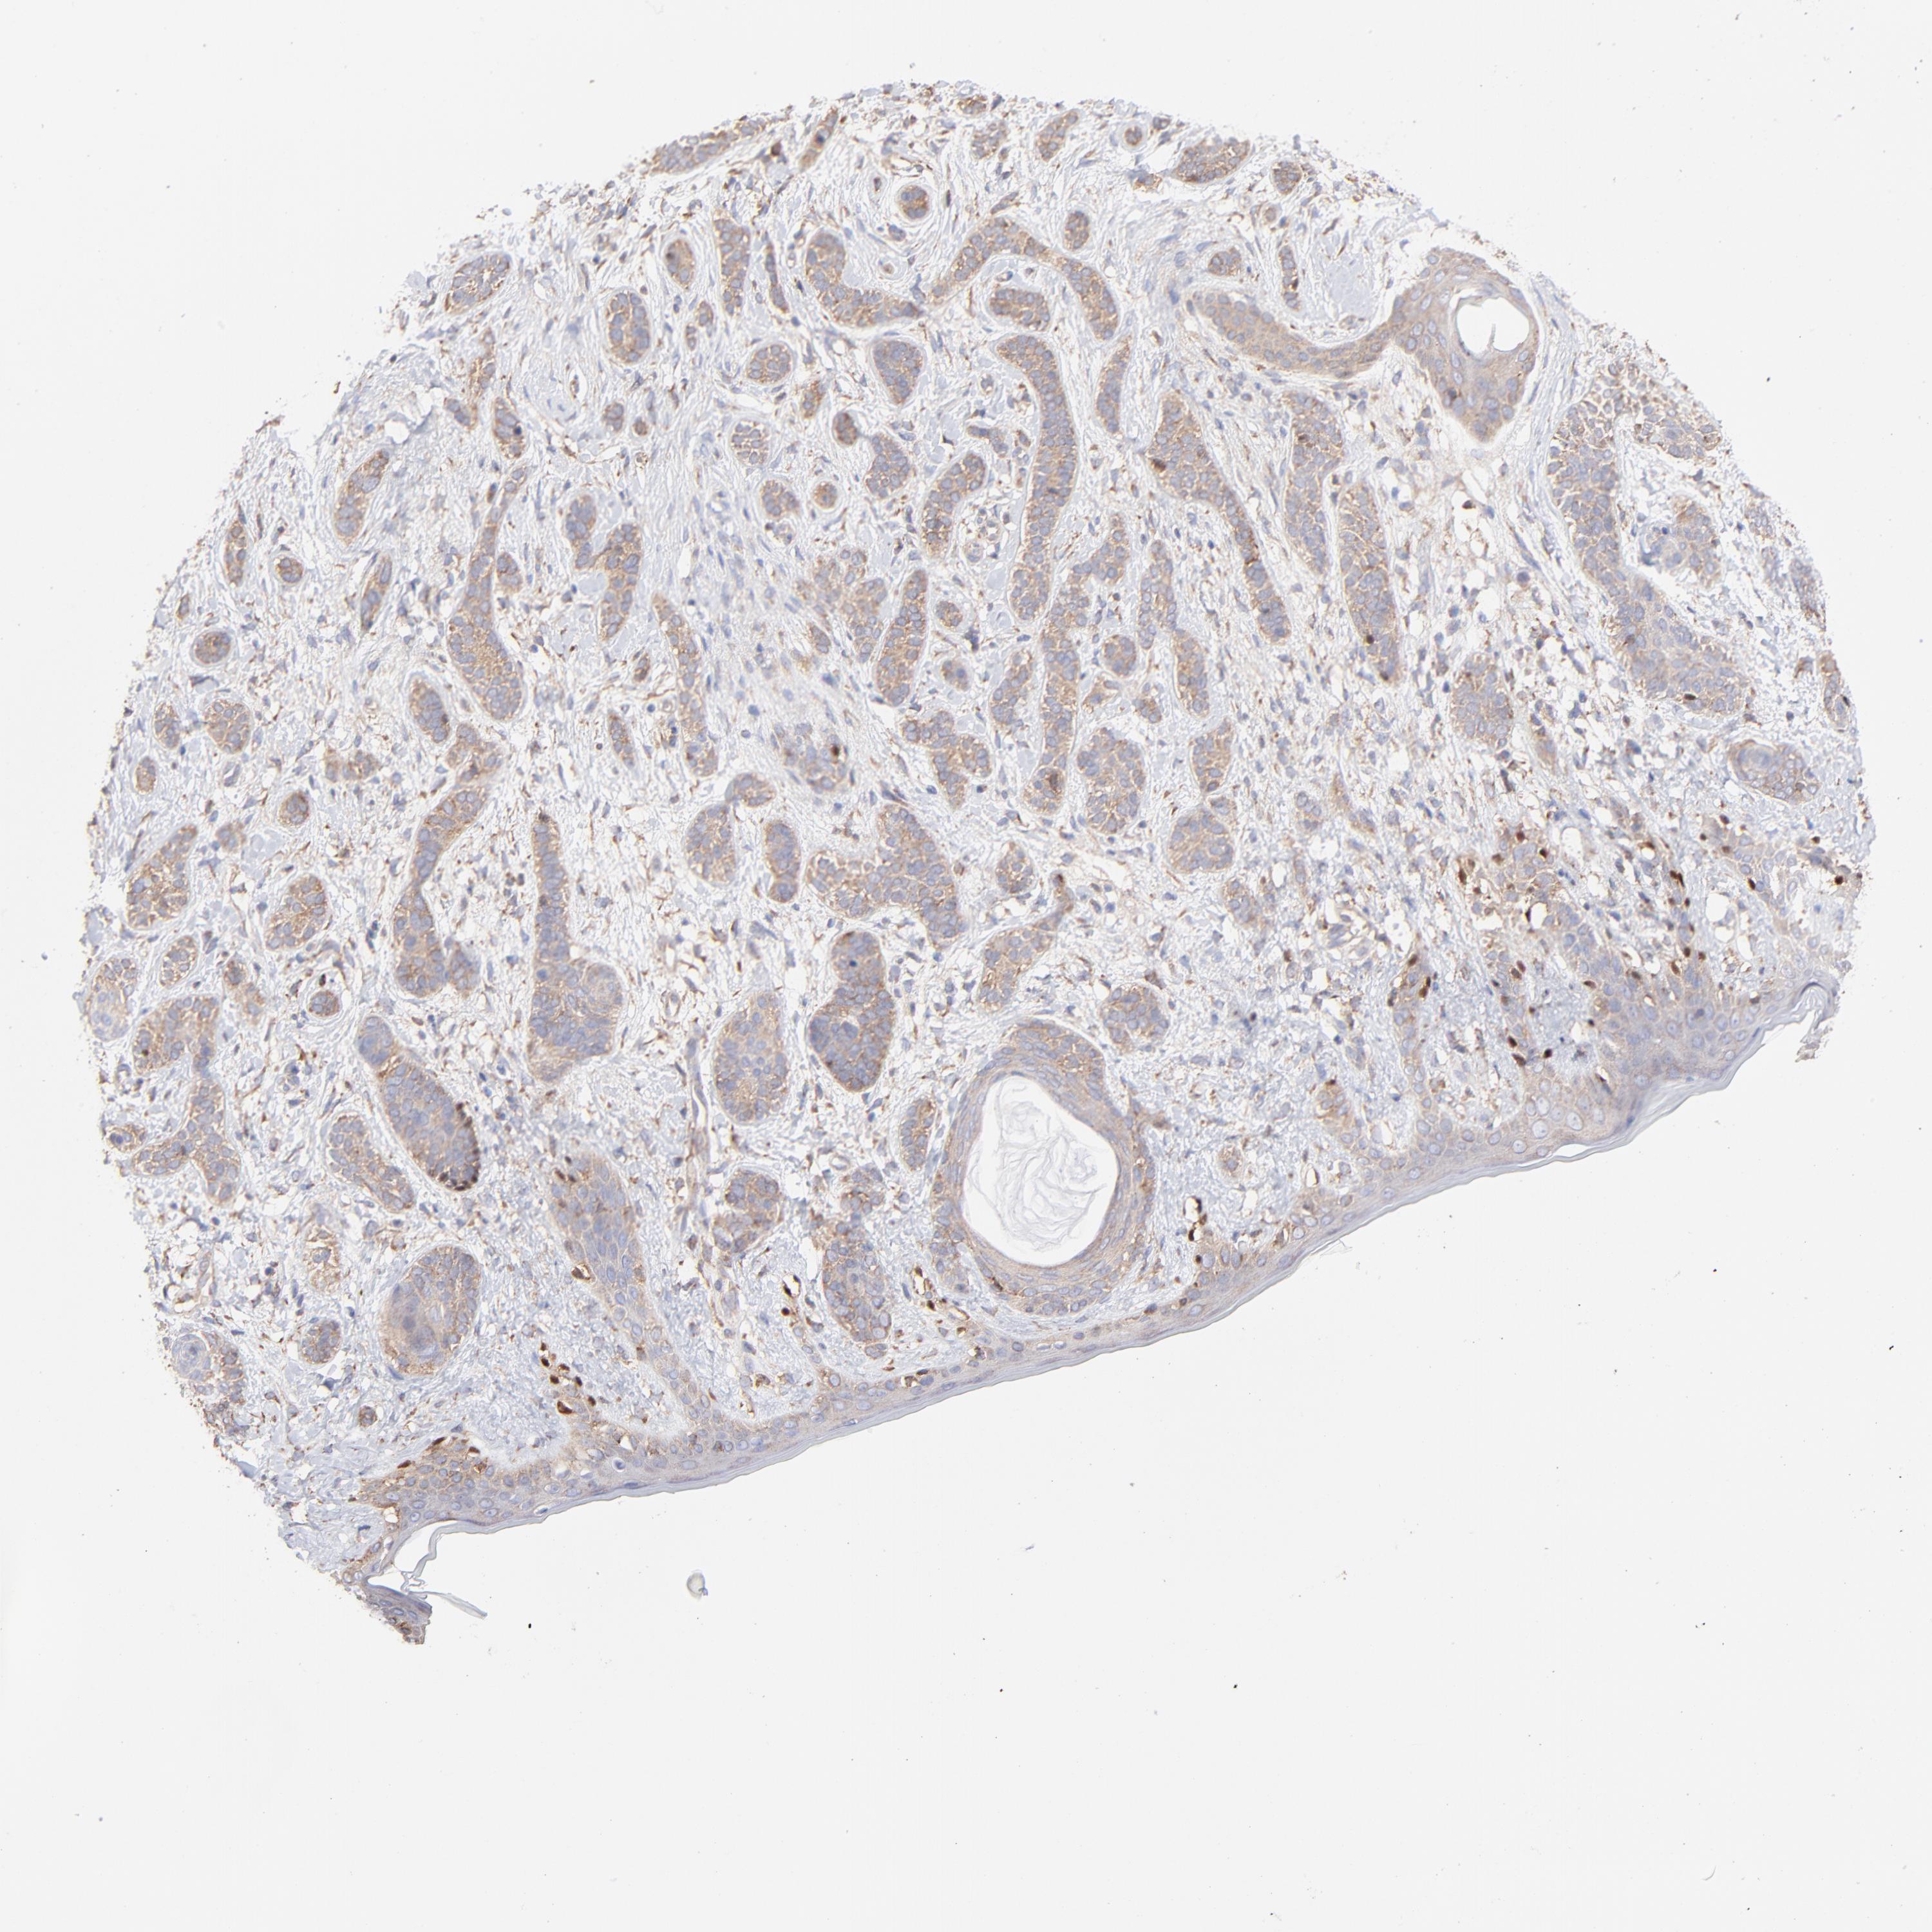

Basal cell and squamous cell cancer

SKIN CANCER - Protein expressioni

A mouse-over function shows sample information and annotation data. Click on an image to view it in a full screen mode. Samples can be filtered based on level of antibody staining by selecting one or several of the following categories: high, medium, low and not detected. The assay and annotation is described here.

Antibody stainingi

Antibody staining in the annotated cell types in the current human tissue is reported as not detected, low, medium, or high, based on conventional immunohistochemistry profiling in selected tissues. This score is based on the combination of the staining intensity and fraction of stained cells.

Each image is clickable and will lead to virtual microscopy that enables deeper exploration of all samples and also displays staining intensity scores, fraction scores and subcellular localization as well as patient and tissue information for each sample.

Antibody HPA002117

Staining

High

Medium

Low

Not detected

Intensity

Strong

Moderate

Weak

Negative

Quantity

>75%

75%-25%

<25%

None

Location

Nuclear

Cytoplasmic/membranous

Cytoplasmic/membranous,nuclear

Squamous cell carcinoma, NOS